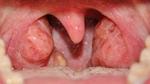

اللوزتان تقعان في آخر تجويف الفم، وهما من الجهاز اللمفاوي في الجسم وتعملان في مساعدة جهاز المناعة في التخلّص، ومنع الجراثيم ومسببات الأمراض المختلفة من الدخول إلى الجسم عن طريق الفم، وتؤدي هاتان اللوزتان هذه الوظيفة بالصورة الطبيعيّة ولكنهما قد يتقاعصان عن أداء هذه المهمّة ويصبحان مصدراً للأمراض والمشاكل في الجسم، وهنا قد يلجأ البعض إلى استئصالهما للتخلّص من الأمراض المتعلقة بهما، ولكن يجب التفكير جيّداً قبل اللجوء إلى هذا الحل.

- تضخّم حجم اللوزتين ممّا قد يؤدي إلى سد مجرى التنفس أحياناً.